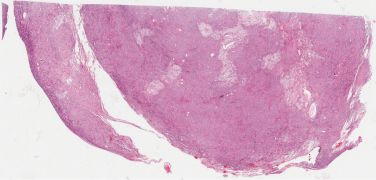

This 23 year old woman had a partial seizure while 36 weeks pregnant.  MRI showed a left frontoparietal mass with calcified and cystic areas with enhancement of the soft tissue component, producing edema and mass effect.  The mass was resected after the patient was delivered.

Sections showed a small cell neoplasm with calcification, sclerotic vessels and cyst formation, which infiltrated adjacent brain.  There were very hyalinized and mineralized regions.  Mitotic count was 2/10 HPF.  The tumor was positive for vimentin, GFAP, and EMA and a few cells stained for NSE.  The tumor was negative for NeuN.  MIB1 was 50%.

The differential diagnosis included pineal tumor/pineocytoma, meningioma, oligodendroglioma, pilocytic astrocytoma, neuroendocrine neoplasm, glioneuronal tumor and ependymoma.  The diagnosis is high grade astroblastoma, on the basis of the immunostaining pattern, which is a new entity in the WHO classification and which does not carry a WHO grade at this time (see Reference).  This rare tumor occurs predominantly in children and young adults (median age 11 y; range 1-58 y).  Its pattern of broad processes extending to sclerosing blood vessels is characteristic and the tumor is positive for vimentin, S100 and GFAP.  MRI findings are important and show a well demarcated, lobulated and calcified enhancing mass.  MIB1 is variable.  The tumors with low-grade histology have a better prognosis than the high-grade tumors.